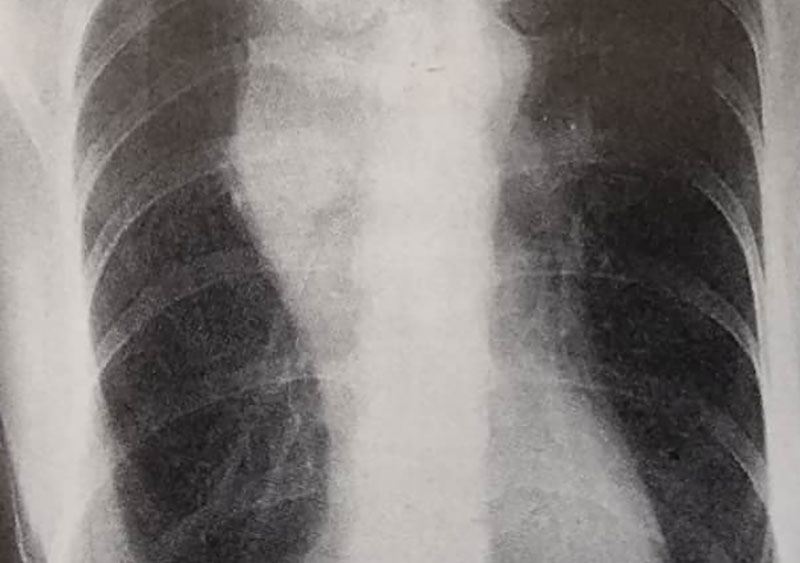

- عکس قفسه سینه (Chest X-ray) (شکل 55d)

این فرد بیماری مدیاستینال داشت (تصویر55d) و با چهار دوره شیمی درمانی و بدنبال آن پرتودرمانی تحت درمان قرار گرفت. اگرچه در رادیوگرافی که 2سال بعد تهیه شد (تصویر55e) علایم بهبودی از بیماری هودجکین نشان داده شد اما شواهدی از افزایش سایه های دوطرفه در نواحی تحتانی دیده می شود و در بیمار پنمونیت ناشی از پرتودرمانی ایجاد شد که به درمان با استروئید پاسخ داد.